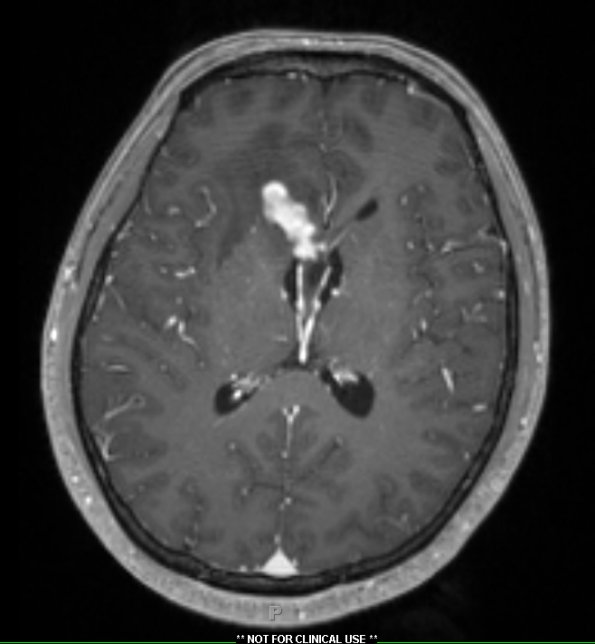

2A3 Germinoma, callosum (Case 2) T1W1 - Copy

T1-weighted image shows enhancement with contrast.